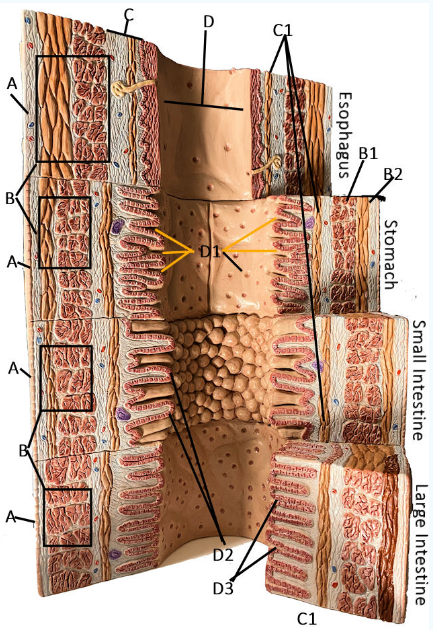

GI Cytology

A

Serosa

B Esophagus

Muscularis externa: skeletal, skeletal/smooth, and smooth, circular and longitudinal

B Stomach

Oblique, circular, and longitudinal smooth muscle

B Small intestine

circular and longitudinal smooth muscle

B large intestine

circular and longitudinal smooth muscle

C

Submucosa: areolar and dense connective tissue

D

Lumen

D1

Gastric glands/pits

D2

Villi of small intestine

D3

Intestinal crypts of large intestine